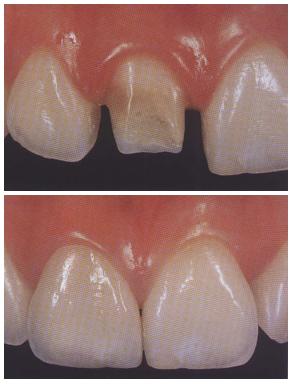

EMPASTE

Se trata de un modo de reparar una pieza dental dañada o con caries y devolverle su forma, función y estética ideal. El dentista retira el material cariado, desinfecta y rellena la zona afectada con un material. Este material de restauración puede ser: composite (del color del diente) o amalgama de plata y mercurio (color metálico). La duración de ambos en boca suele ser de 5 a 8 años aproximadamente, aunque depende del tipo de paciente: higiene bucal, zona y pieza afectada, si rechina los dientes o muerde objetos.